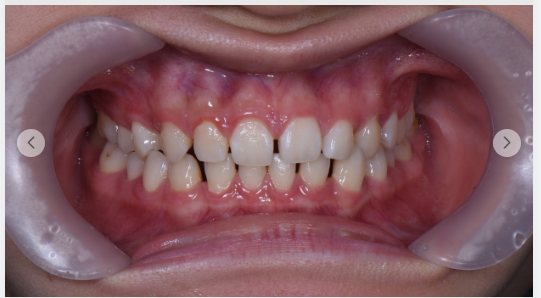

이 환자분의 경우, 하악골이 상대적으로 발달하여 얼굴이 길어 보이는 골격성 부정교합이었습니다.

2025년 8월 6일, 본격적인 치료가 시작되었습니다.

비포 앤 애프터 사진을 나란히 놓고 보니, 변화는 명확했습니다.

위아래 치아의 물림이 개선되었고, 얼굴의 좌우 균형이 잡히기 시작했으니까요.